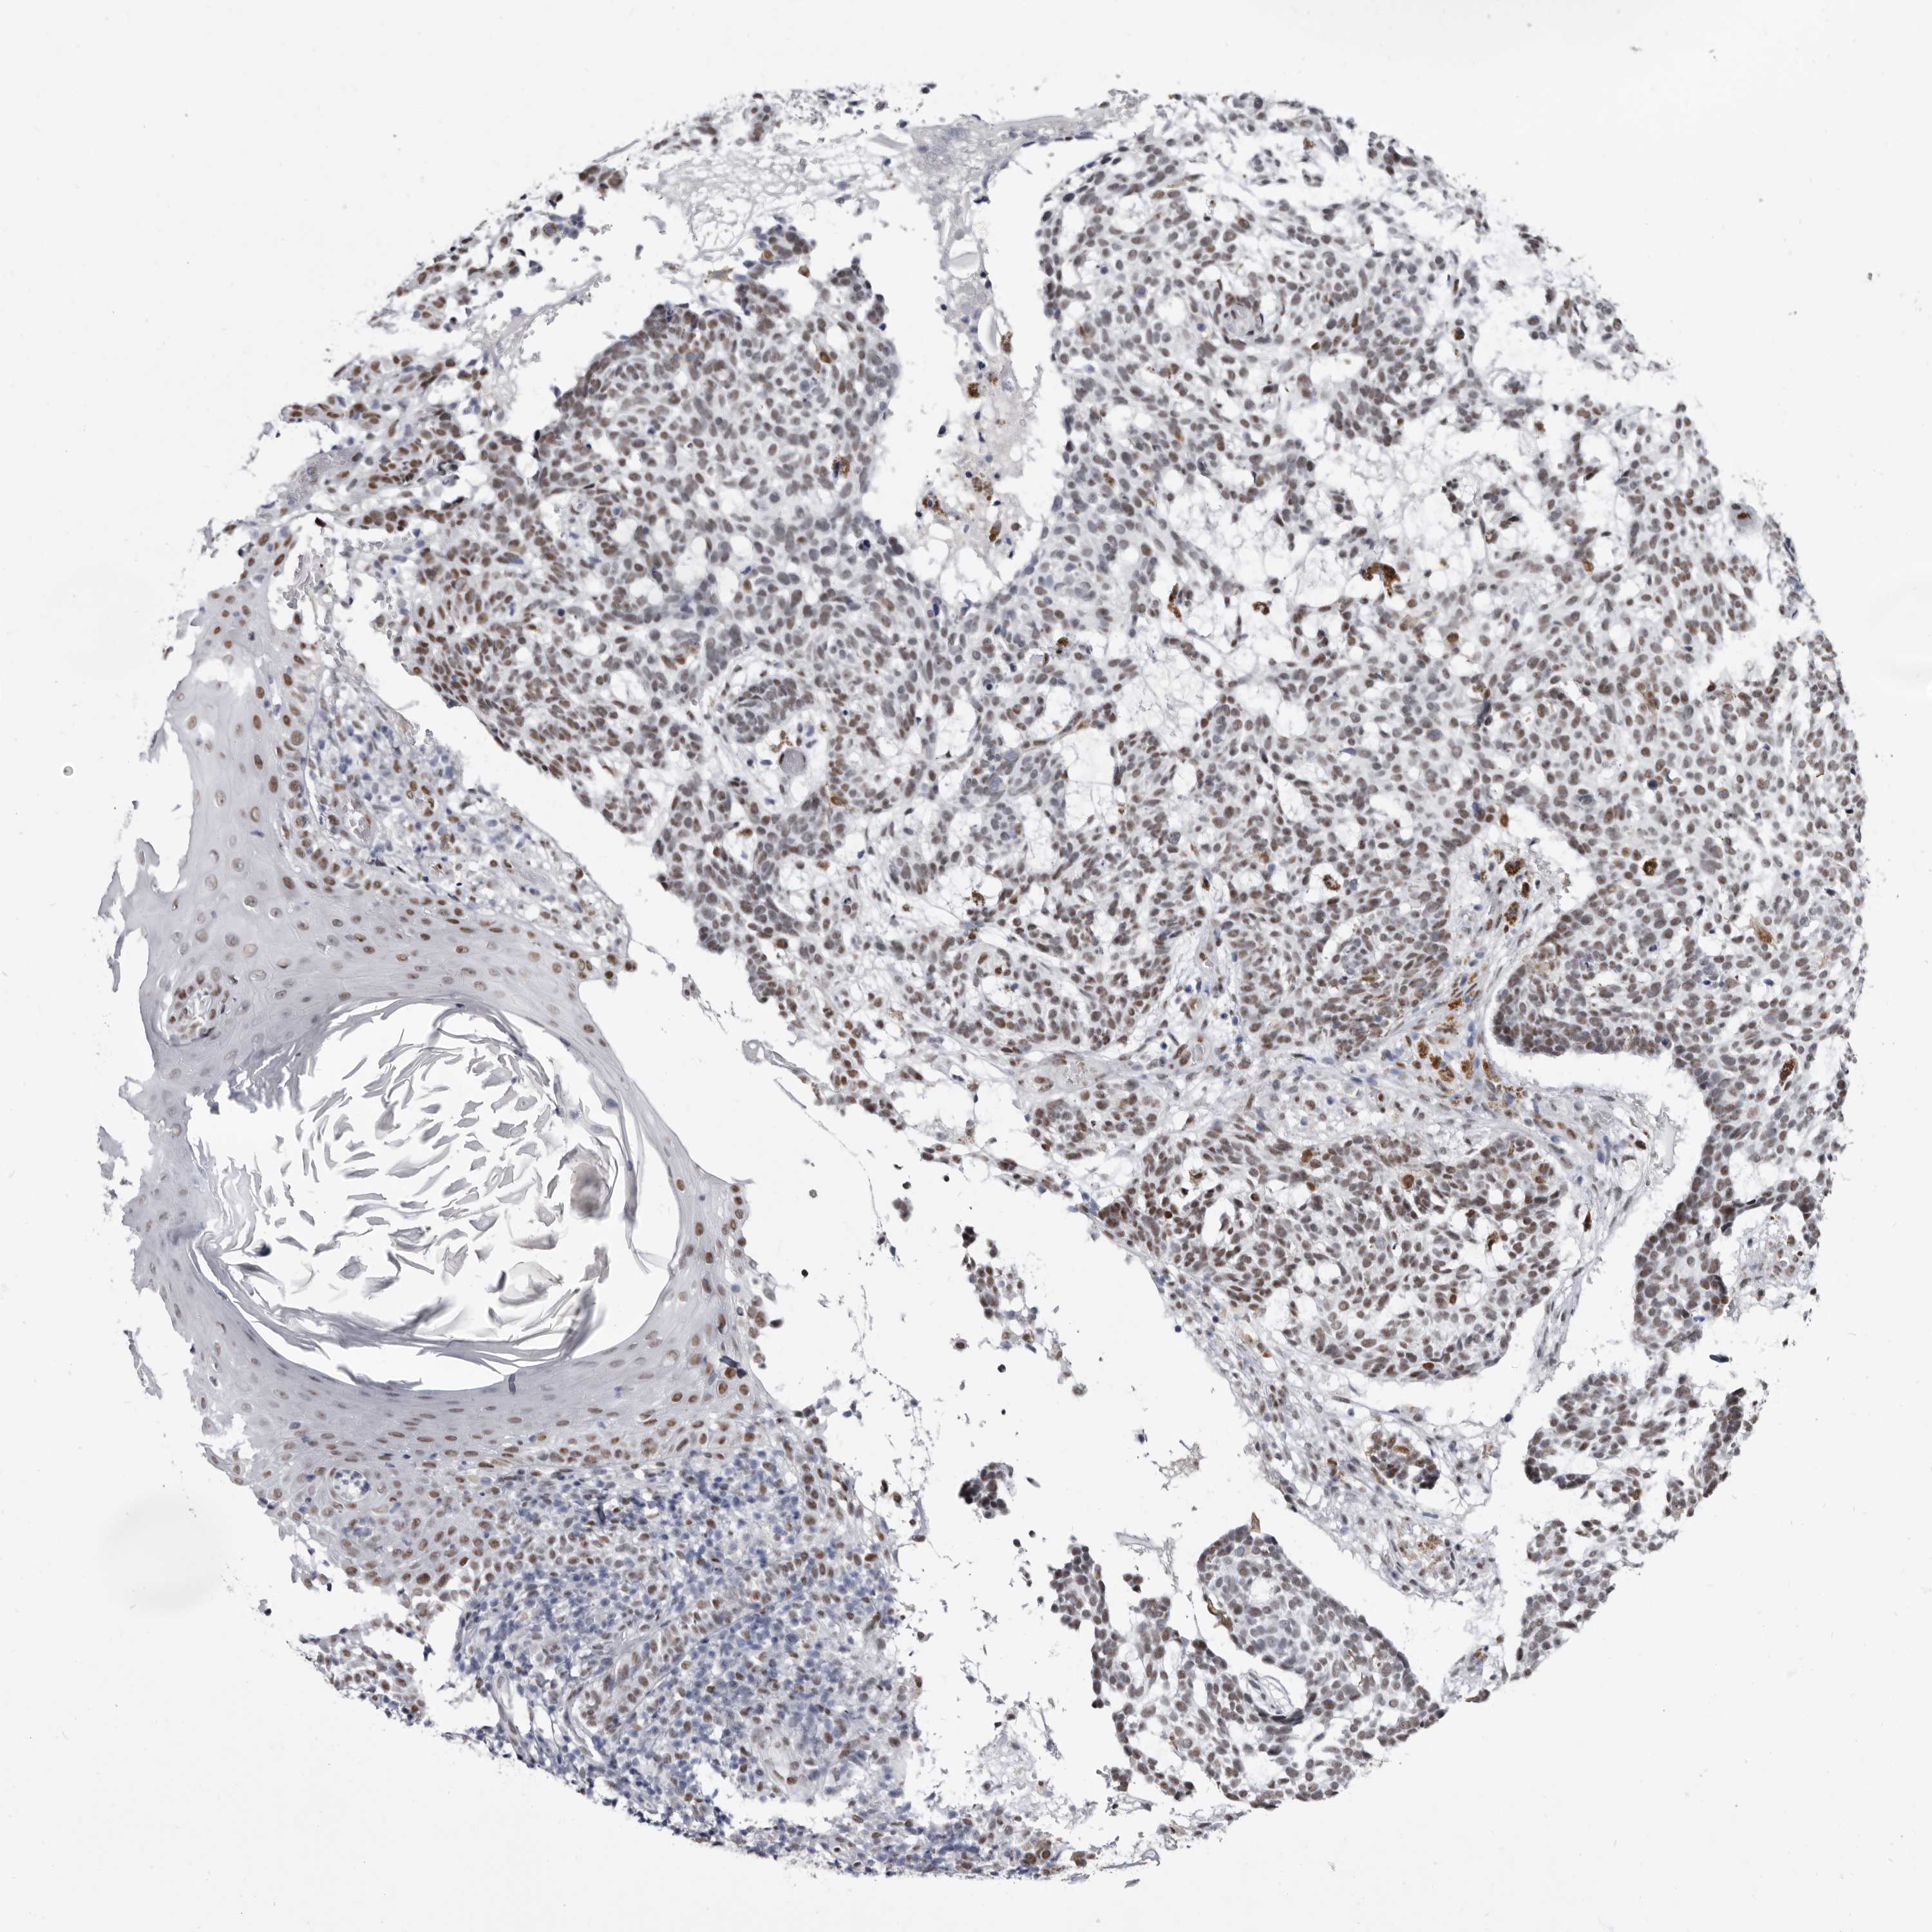

SKIN CANCER - Protein expressioni

A mouse-over function shows sample information and annotation data. Click on an image to view it in a full screen mode. Samples can be filtered based on level of antibody staining by selecting one or several of the following categories: high, medium, low and not detected. The assay and annotation is described here.

Antibody stainingi

Antibody staining in the annotated cell types in the current human tissue is reported as not detected, low, medium, or high, based on conventional immunohistochemistry profiling in selected tissues. This score is based on the combination of the staining intensity and fraction of stained cells.

Each image is clickable and will lead to virtual microscopy that enables deeper exploration of all samples and also displays staining intensity scores, fraction scores and subcellular localization as well as patient and tissue information for each sample.

Antibody HPA028461

Basal cell carcinoma